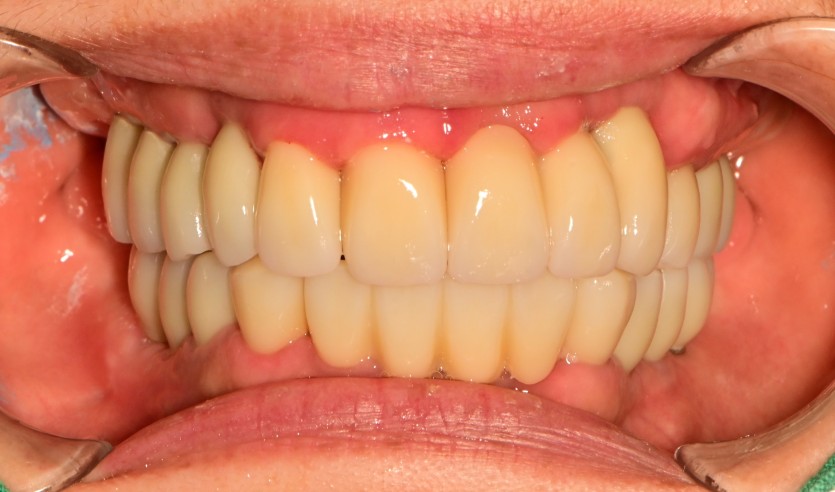

만 56세 전체 임플란트 증례

전체 임플란트 증례입니다.

17개의 임플란트로 완성하였습니다.